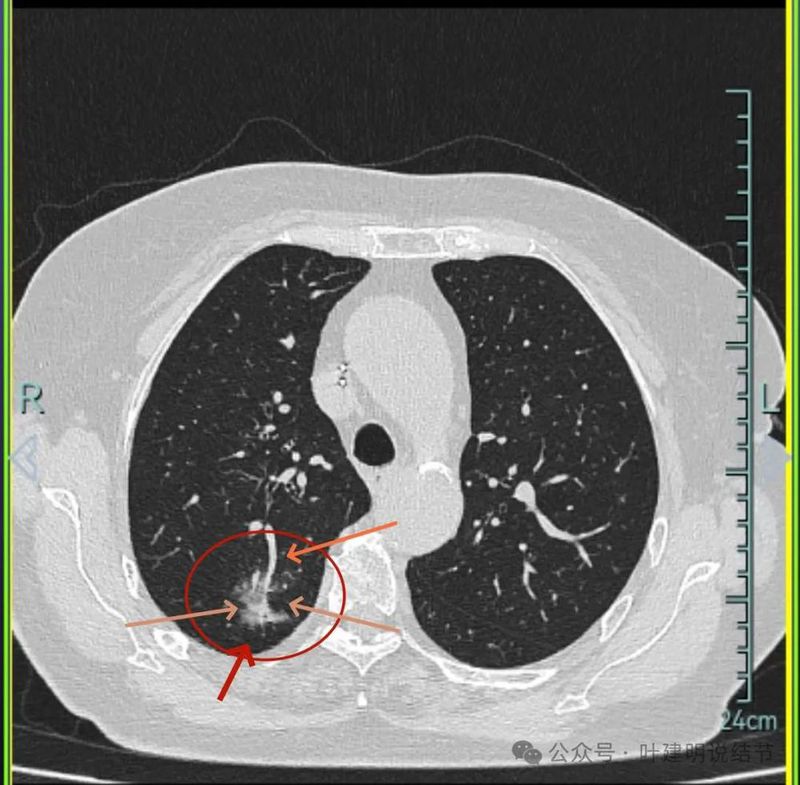

主病灶连续层面展示分析:

病灶出现,磨玻璃密度,轮廓与边界均清楚,灶内密度稍不均。

有明显血管进入,表面分叶,边缘不平,整体轮廓清。

边缘毛刺、表面不平、灶内偏实性成分、分叶明显,整体轮廓与瘤肺边界较为清楚。

灶内细支气管扩张、边缘毛刺较为锐利、有明显磨玻璃成分,磨玻璃成分的瘤肺边界清楚,病灶分叶明显。

灶内密度杂乱不均,内有小空泡征,表面不平。

灶内血管增粗穿行、磨玻璃成分明显,轮廓较清。

血管进入,磨玻璃成分,支气管扩张,边缘不平。

典型混合密度病灶,中间部分密度高偏实性,外围部分磨玻璃密度,两者之间交错存在,说明偏实性部分有侵袭性。磨玻璃成分与正常肺组织之间界限清楚,表面分叶,部分边缘毛刺,整体轮廓清。是非常符合恶性的影像表现。

灶内磨玻璃成分明显,并有异常增粗血管僵硬穿行于病灶内,支气管有扩张通气征,瘤肺边界清楚,实性成分明显。